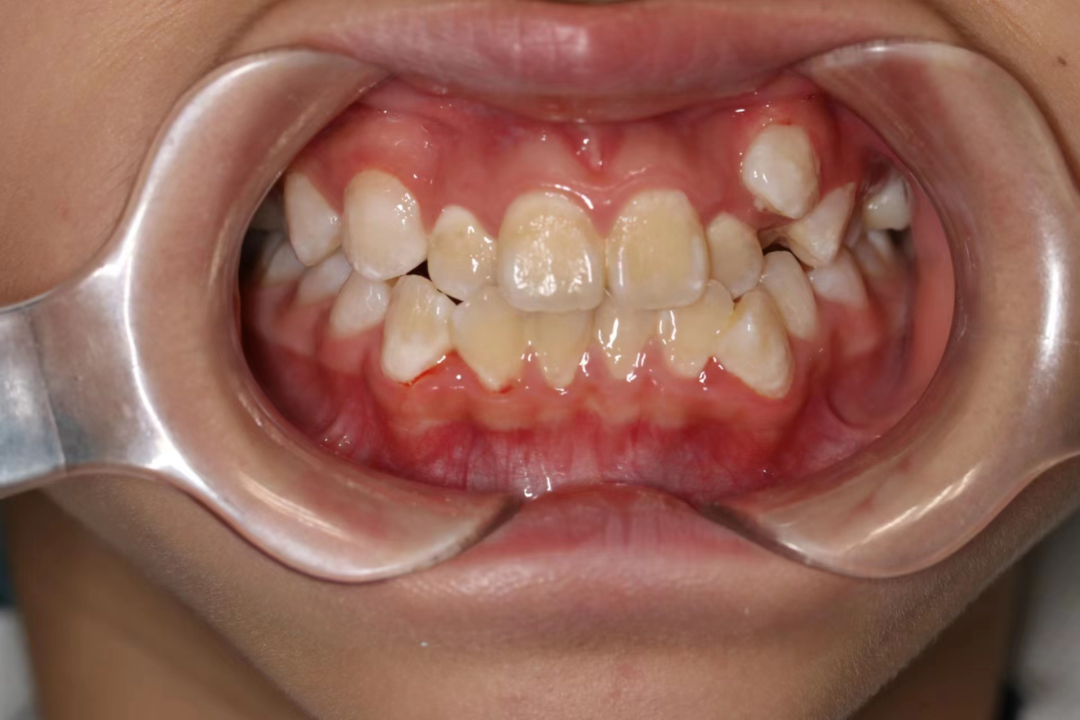

牙列拥挤

患者口腔内牙齿拥挤错位排列不齐,口腔内过于拥挤的牙齿发生牙周病及龋齿的概率比整齐的牙齿高出数倍。牙列拥挤不仅影响口腔问题,美学角度也大打折扣。